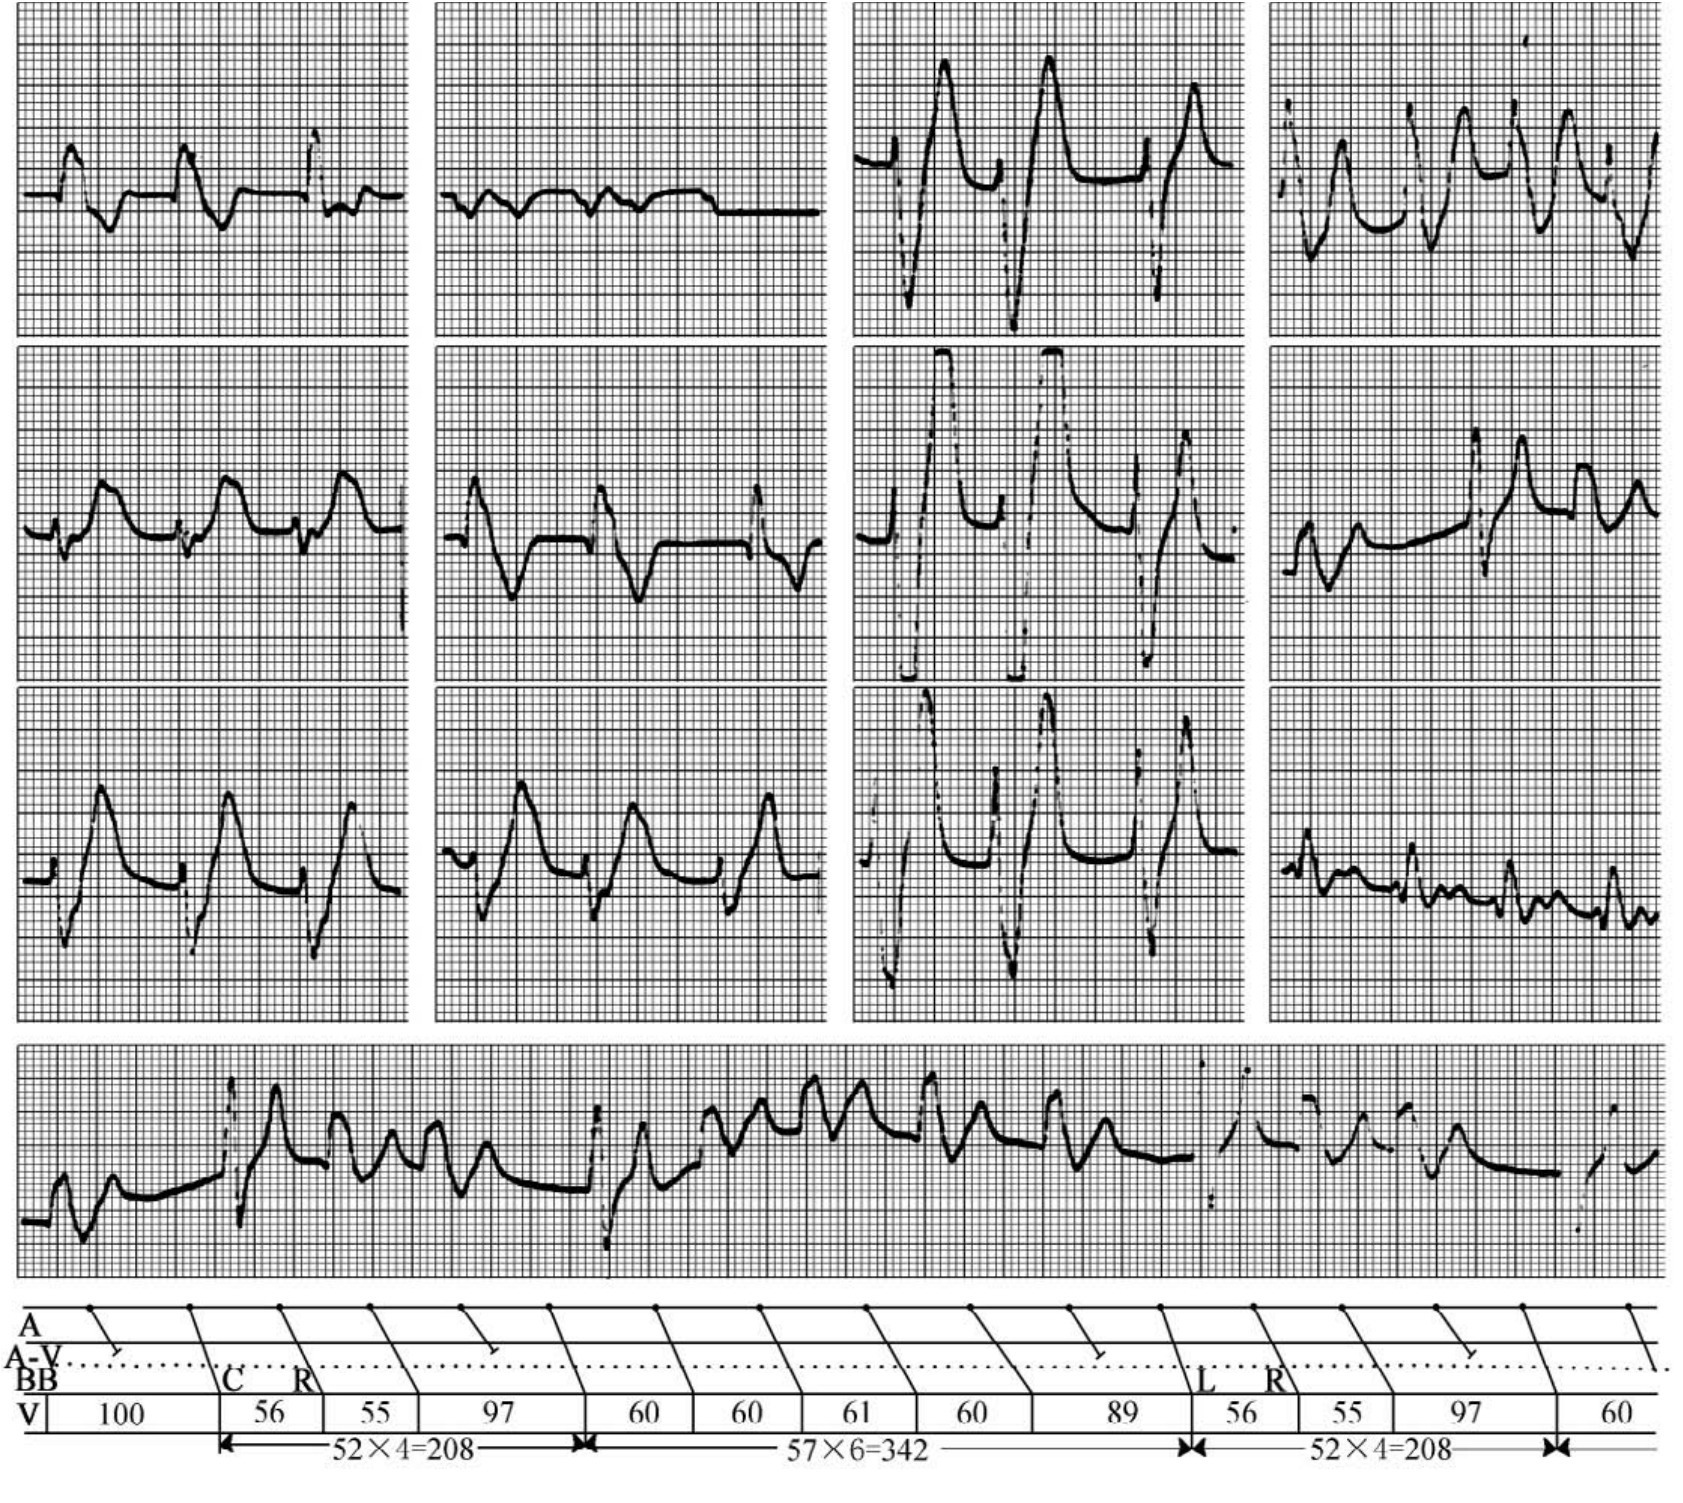

1.7.3.7.2第二节 复杂、疑难心电图梯形图诊断技术及应用

1.7.3.7.3第三节 宽QRs波群心动过速的诊断与鉴别诊断

1.7.3.7.4第四节 快速识别宽QRs心动过速为室性心动过速简易五步法